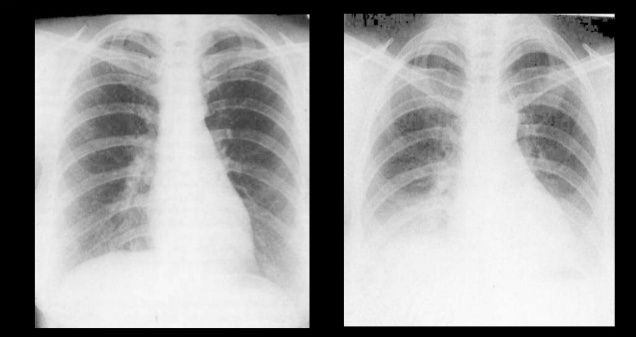

3. Inspiratory vs Expiratory

| Inspiratory vs Expiratory Chest Xray |

If anterior end of 6th or 7th rib reaches mid-clavicular line of diaphragm, it is Inspiratory Xray.